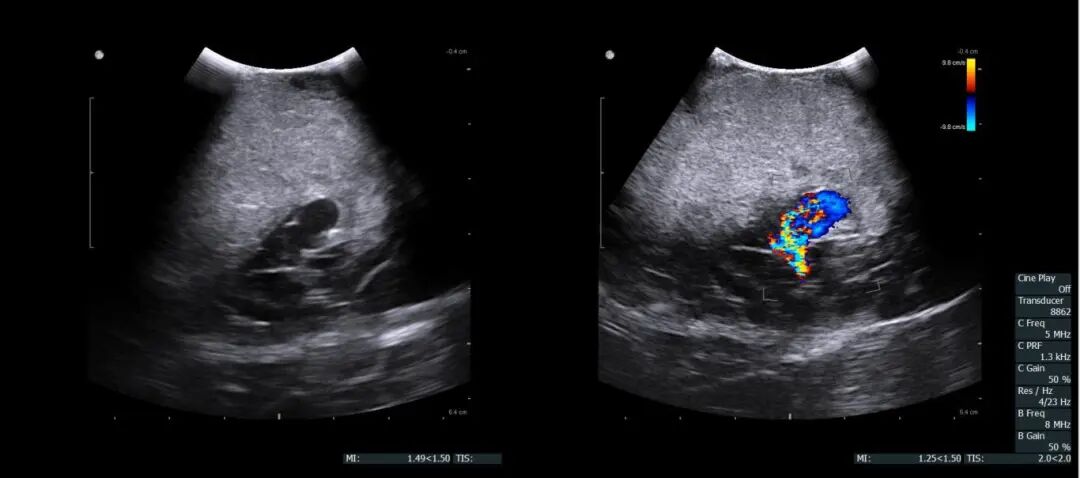

术中超声精准探查动脉瘤及周边血肿

在麻醉科手术室的紧密配合下,樊明德及主任医师赵旭在显微镜下为婷婷精准实施手术。术中超声仔细探查脑内血肿及动脉瘤的位置后,血肿被逐步清除,破裂的动脉瘤和异常的动静脉瘘口逐渐显露,小心翼翼避开重要神经和血管,精准切除动脉瘤,成功封闭动静脉瘘口。整个过程紧张有序,历时3小时顺利完成。